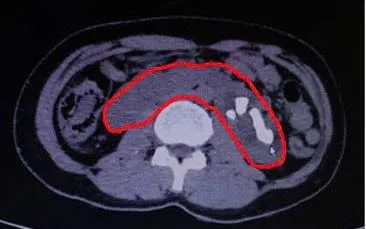

Người bệnh P.T.L., (42 tuổi) nhập Bệnh viện Việt Nam - Thụy Điển Uông Bí (Quảng Ninh) trong tình trạng đau quặn vùng mạn sườn trái, đau lan xuống vùng bụng dưới. Qua thăm khám, siêu âm và CT Scanner, các bác sĩ phát hiện người bệnh có dị dạng thận móng ngựa - một dị dạng bẩm sinh khiến hai thận dính nhau ở cực dưới tạo hình "móng ngựa" kèm theo sỏi thận lớn.

Trước tình hình đó, kíp phẫu thuật đã tiến hành thực hiện kỹ thuật tán sỏi qua da - một phương pháp ít xâm lấn, an toàn và hiệu quả